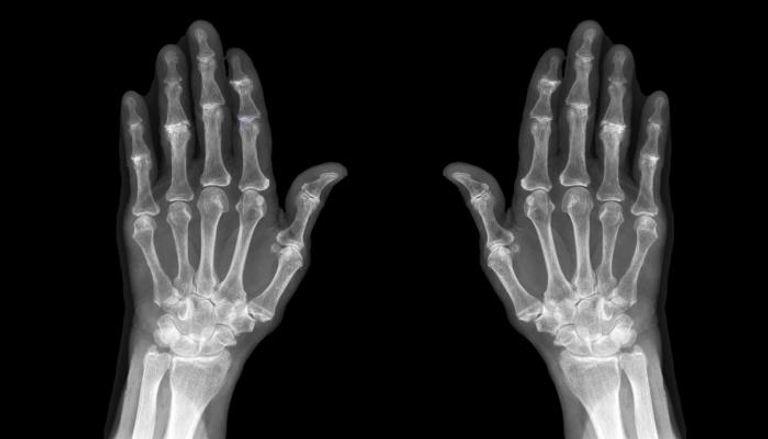

علامة في اليد تكشف الإصابة بهشاشة العظام

يحدث الفصال العظمي ، الذي يُطلق عليه أيضًا مرض المفاصل التنكسية أو التهاب المفاصل "البلى" ، عندما يبدأ الغضروف الموجود داخل المفصل الذي يسند نهايات العظام في التآكل بمرور الوقت، غالبًا ما تحدث التغييرات ببطء وبشكل تدريجي بمرور الوقت، وفقًا لمايو كلينك ، فإنه يؤثر بشكل شائع على المفاصل في اليدين والركبتين والوركين والعمود الفقري.

وتشير CreakyJoints إلى أن هشاشة العظام يمكن أن تؤدي إلى تصلب "خاصة في الصباح". يشرح ذلك ، "يمكن أن يسبب هشاشة العظام الألم ، والتصلب (خاصة في الصباح) ، والتورم ، وألم المفاصل في اليدين." تقول المؤسسة الخيرية أن ألم اليد المرتبط بالفصال العظمي يمكن أن يشير أحيانًا إلى تقلص دوبويتران ، وهي حالة غير مؤلمة تسبب أو أكثر من الأصابع للانحناء باتجاه راحة اليد ، علاوة على ذلك ، يمكن أن تؤدي الحالة إلى نمو عظام إضافية في المفاصل ، وتسمى أيضًا بالنباتات العظمية.